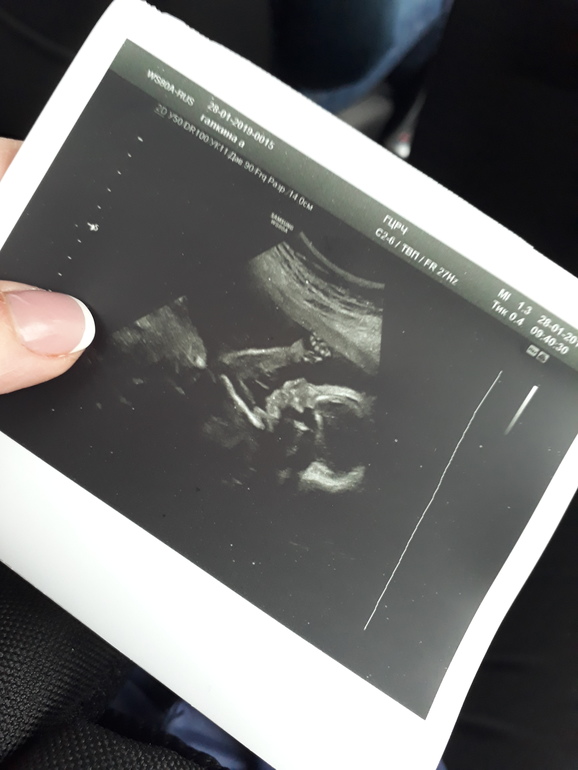

УЗИ, КТГ, доплерсходила сегодня на второй скрининг, слава Богу все хорошо, вес 416 гр, я очень переживала, но все хорошо) подтвердили мальчика

сходила сегодня на второй скрининг, слава Богу все хорошо, вес 416 гр, я очень переживала, но все хорошо) подтвердили мальчика